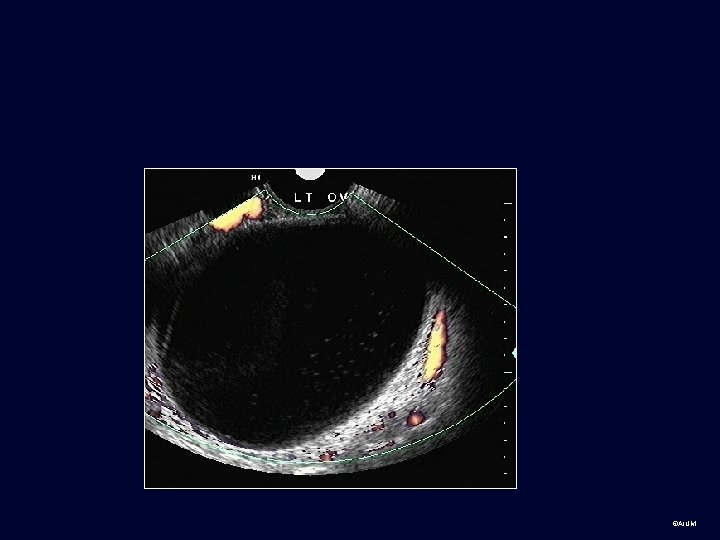

Practice cases for students: Normal and abnormal • Transabdominal, transvaginal or can’t tell? • Body part? • Normal or abnormal (provide diagnosis or Ddx if possible) ©AIUM

Group 2 ©AIUM

©AIUM

©AIUM